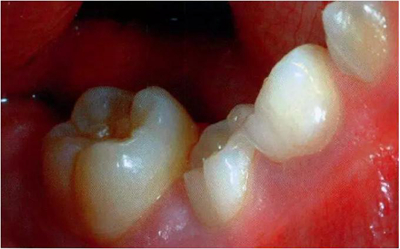

圖1:輕度下沉的臨床像

圖2:中度下沉的臨床像